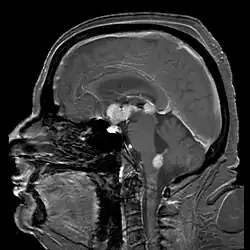

Las localizaciones más frecuentes son: Hemisferios (31%), cuerpo calloso (15%), ganglios basales y tálamo (15%) y cerebelo (14%). Puede darse también en el fluido cerebroespinal y en los ojos (linfoma ocular). Además, no es extraño encontrar este tumor en varias partes del hemisferio cerebral, ya que puede esparcirse a través de todo el sistema nervioso central.[2]

Las lesiones frecuentes a menudo afectan a la sustancia gris profunda, así como a la sustancia blanca y a la corteza. La diseminación periventricular es frecuente. Los tumores están bien definidos a comparación con las neoplasias gliales, pero no tan delimitados como las metástasis y por lo general muestran áreas extensas de necrosis central. En el tumor, las células malignas infiltran el parénquima del encéfalo y se acumulan alrededor de los vasos sanguíneos. Las tinciones de reticulina demuestran que las células infiltrantes están separadas una de otra por un material que se tiñe con plata; este patrón, denominado “el anillo”, es característico del linfoma encefálico primario. Cuando los tumores se originan en el seno inmunodepresión, pueden utilizarse varios marcadores de infección vírica por Epstein-Barr como ayuda para el diagnóstico.